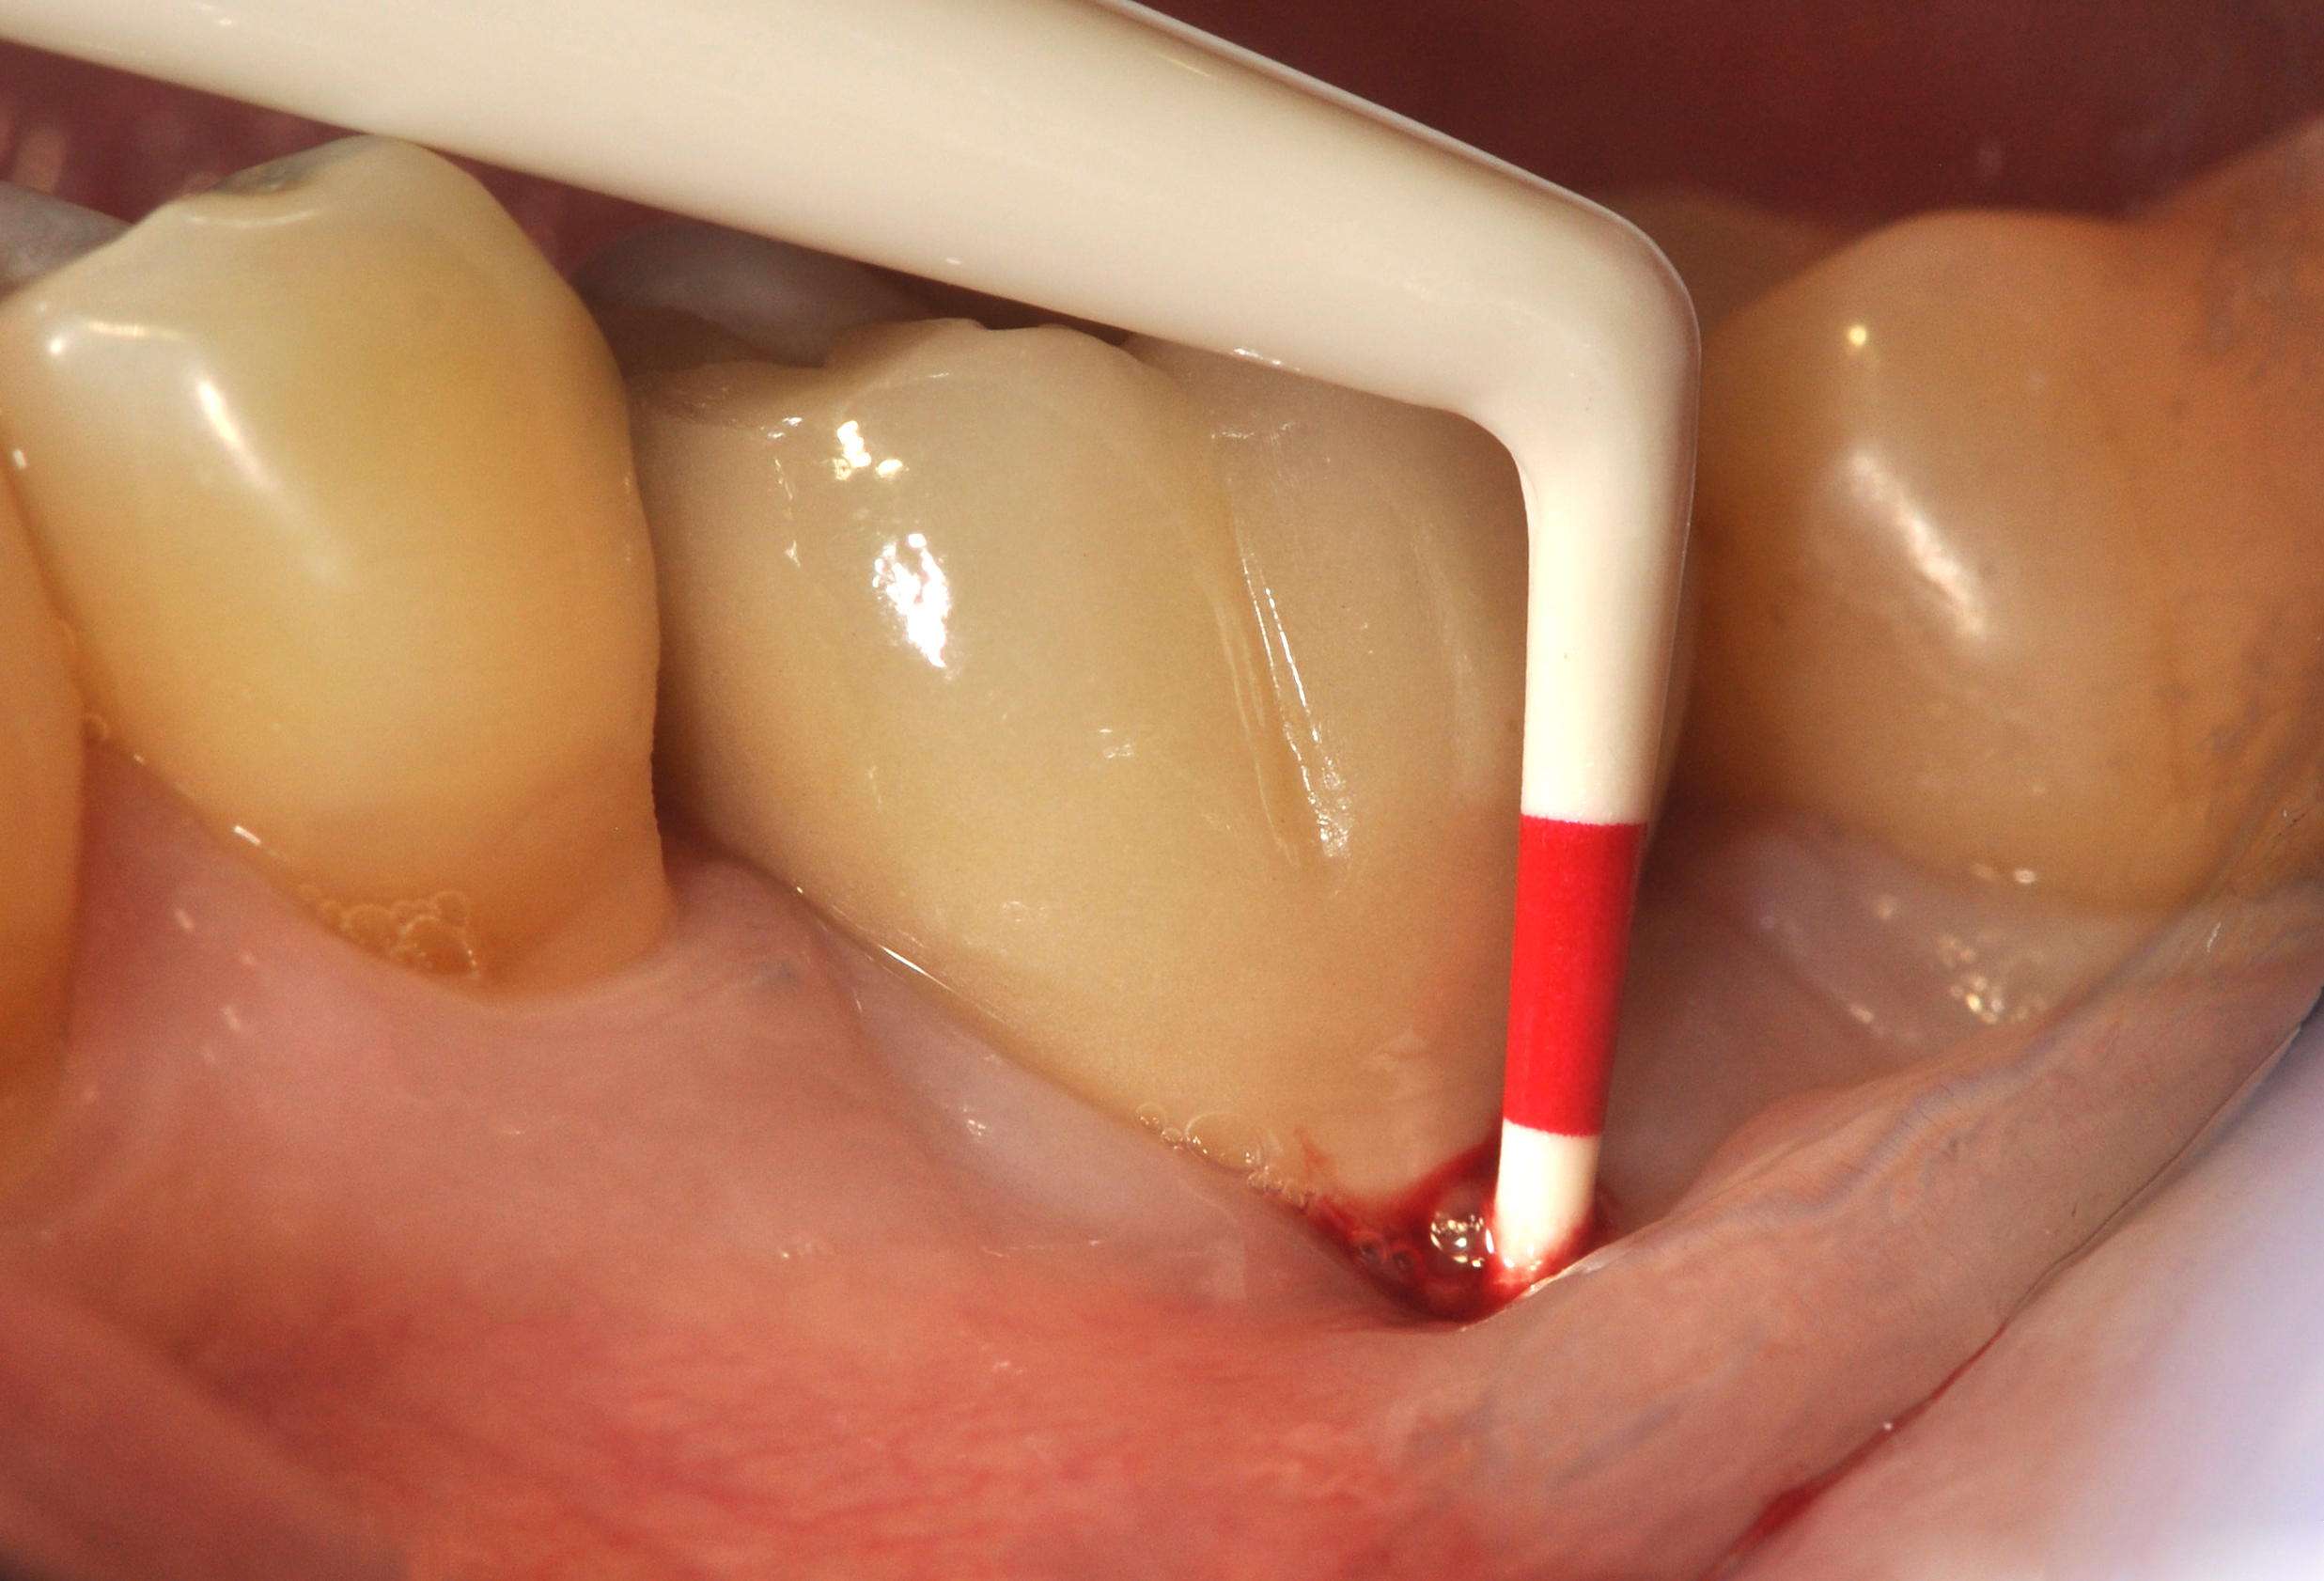

Fig 15. The implant-supported restoration of tooth No. 19 presented with a lack of attached keratinized gingiva, shallow buccal vestibule, and 2 mm of buccal recession.

Figure 15

Fig 16. The restoration exhibited an 8-mm pocket upon probing, with bleeding on the buccal aspect.

Figure 16

Clinical examination showed 2 mm of buccal recession with a shallow vestibule and absence of keratinized attached gingiva against the crown with 8 mm of circumferential pocketing accompanied by bleeding upon probing (Figure 15 and Figure 16). A periapical radiograph showed a symmetrical vertical osseous defect causing the loss of 50% of the bone around the implant (Figure 17). Because the patient had made a significant investment of time and finances to replace her lost tooth with the implant, she desired that the implant and restoration be retained, if feasible.